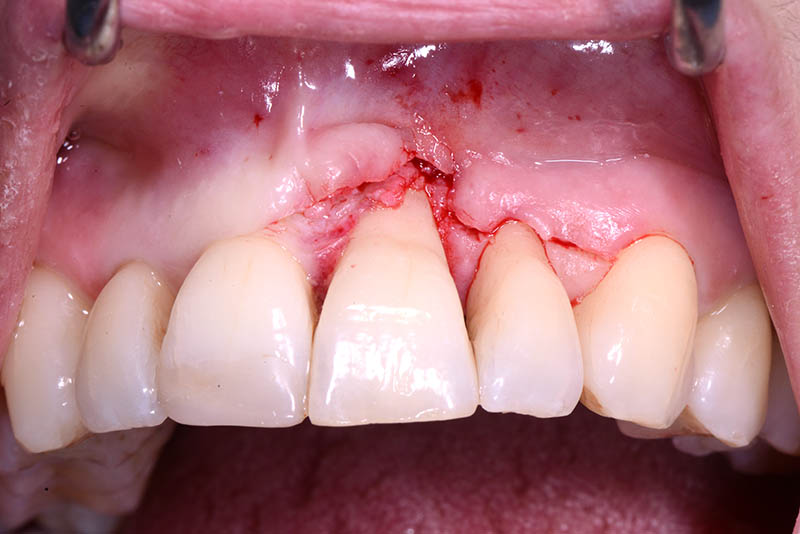

At the end of the orthodontic treatment, a coronally advanced flap was performed according to the De Sanctis and Zucchelli technique, involving papilla preservation and connective tissue grafting, to restore the gingival contour and the papilla between teeth 21 and 22.

connective graft

Emdogain Straumann